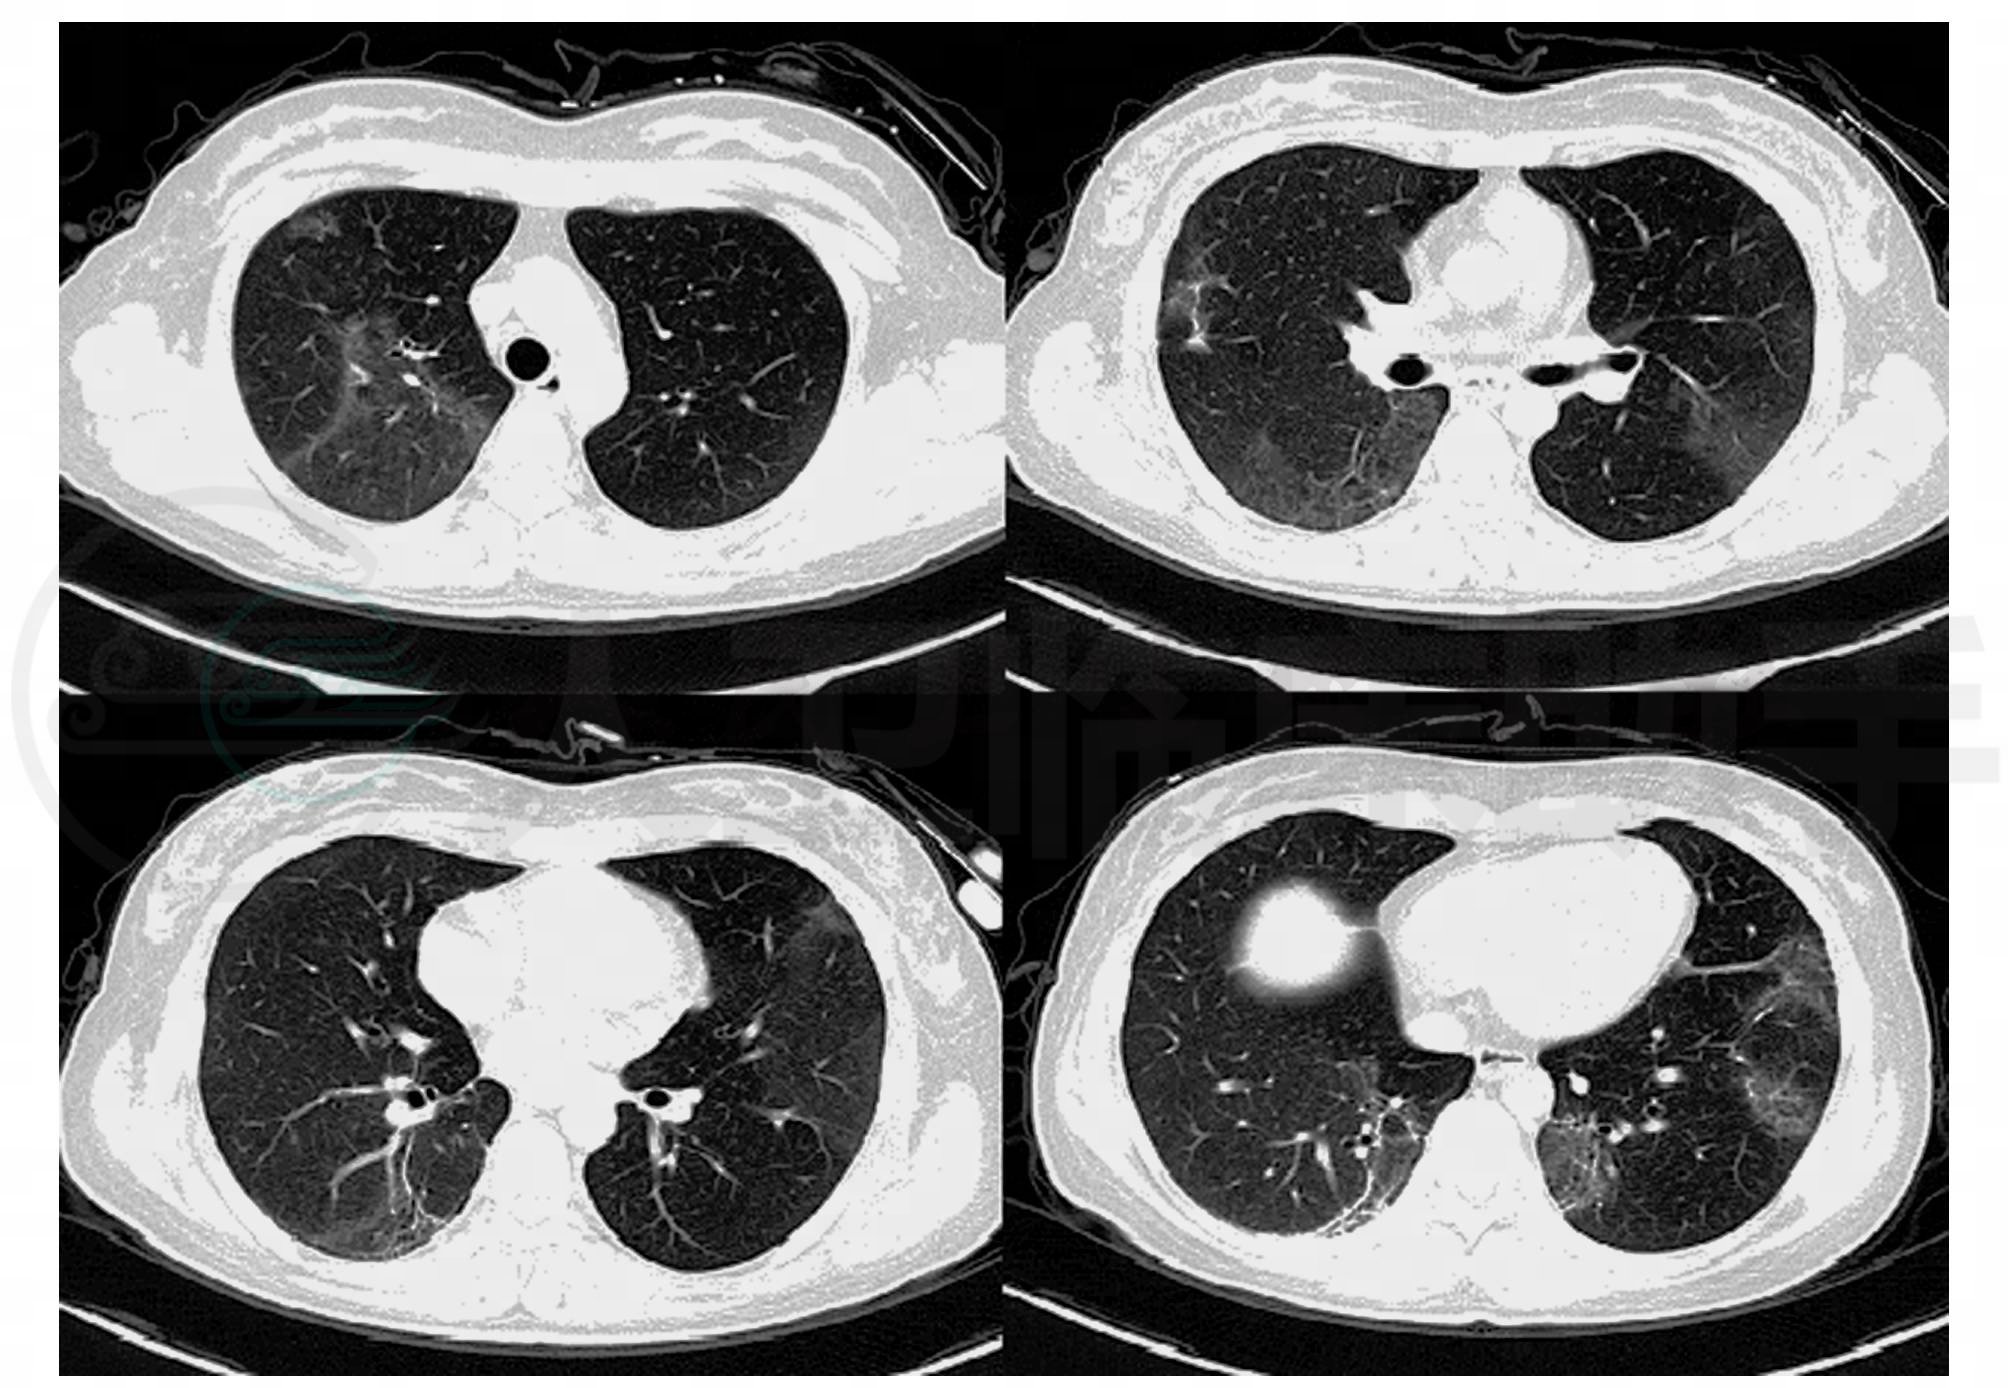

后予患者泼尼松30mg日一次口服,一周后复查肺CT,患者肺部影像较前明显吸收(图2)。临床表现,影像学及TBLB病理结果,结合激素治疗效果明显,支持隐源性机化性肺炎诊断,故予患者泼尼松片30mg口服治疗共1个月,并依据治疗效果逐渐调整口服激素治疗剂量至停用。

图2 双肺病变明显吸收